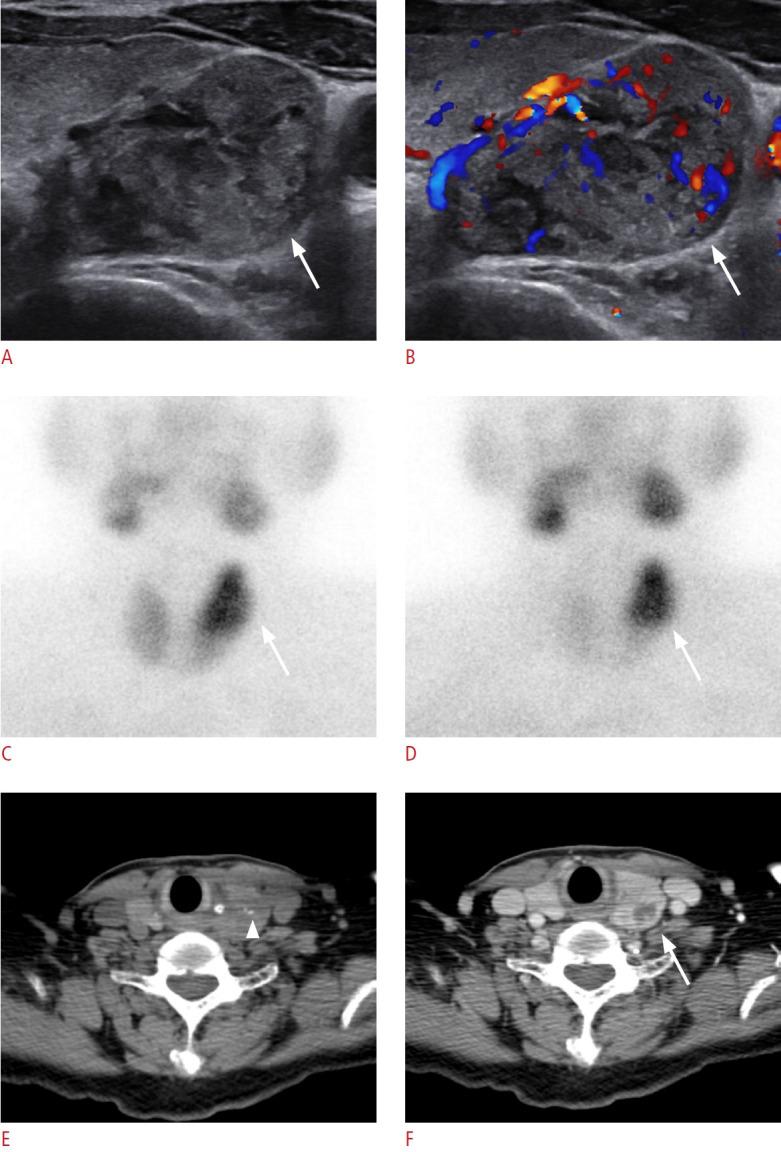

The parathyroid glands play a key role in maintaining calcium-phosphate homeostasis by secreting parathyroid hormone (PTH). Hyperparathyroidism, characterized by the inappropriate overproduction of PTH, is classified as primary, secondary, or tertiary according to its pathophysiology. Although diagnosis is principally biochemical, imaging is essential for accurately localizing hyperfunctioning glands. Precise localization allows for focused minimally invasive surgery, reduces the risk of persistent or recurrent disease, and avoids unnecessary bilateral neck exploration. Current techniques include high-resolution ultrasonography, 99mTc-sestamibi scintigraphy with single-photon emission computed tomography/computed tomography (CT), four-dimensional CT, magnetic resonance imaging, and positron emission tomography/CT with tracers such as 18F-fluorocholine. Parathyroidectomy remains the mainstay of treatment; however, recent advances in thermal ablation have expanded treatment options for patients unsuitable for surgery.

甲状旁腺通过分泌甲状旁腺激素(PTH)在维持钙磷稳态中起关键作用。甲状旁腺功能亢进症的特征是PTH分泌过多,根据其病理生理学可分为原发性、继发性或三发性。虽然诊断主要依靠生化检查,但影像学检查对于准确定位功能亢进的腺体至关重要。精确的定位有助于进行有针对性的微创手术,降低持续性或复发性疾病的风险,并避免不必要的双侧颈部探查。目前的技术包括高分辨率超声检查、99mTc-甲氧基异丁基异腈闪烁显像联合单光子发射计算机断层扫描/计算机断层扫描(CT)、四维CT、磁共振成像以及使用18F-氟胆碱等示踪剂的正电子发射断层扫描/CT。甲状旁腺切除术仍然是主要的治疗方法;然而,热消融技术的最新进展为不适合手术的患者扩展了治疗选择。